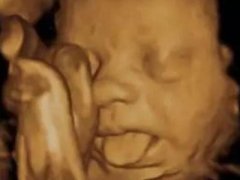

胎宝宝竟在代妈肚子里做这么多事

前几天我随手翻了翻以前的朋友圈,看到mini包第一次打嗝,第一次胎动,还有四维照片里扮鬼脸的小模样,嘴角就不自觉上...

四维彩超那么贵不懂这些就白做了

无论你现在是否已经怀孕了,产检的重要性都是知道。前几天我给大家分享了如何看懂尿检单和血检单。是不是还有一个一个...